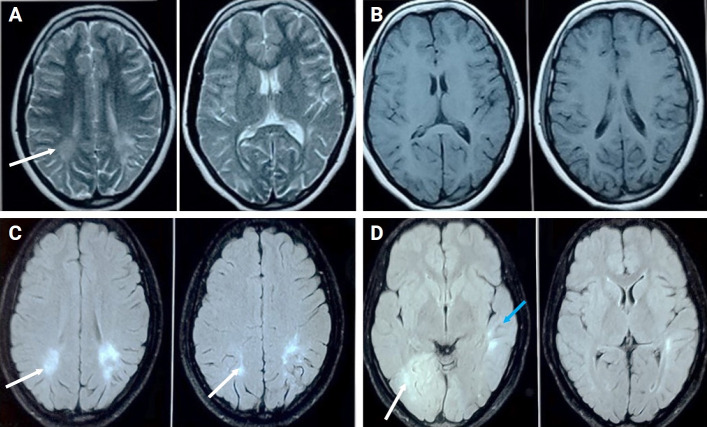

亚急性硬化性全脑炎(SSPE)是一种罕见的进行性神经退行性疾病,由持续的异常麻疹病毒感染引起。其特征是行为改变,认知能力下降,学习成绩下降,视力障碍,局灶性或全身性癫痫发作,肌阵挛,痉挛,失语和运动障碍,最终导致植物人状态。以拟声失联、视共济失调和动眼肌失用症为特征的巴林氏综合征作为SSPE的初始表现特征是罕见的。SSPE患者的自主神经功能障碍归因于中枢自主神经受累,心率变异性降低是心律失常和心源性猝死的预测因子。我们报告一个不寻常的情况下,一个22岁的男性提出的特点提示巴林氏综合征。首次出现症状6个月后出现肌阵挛和认知能力下降,并伴有自主神经功能障碍。此后,症状迅速恶化。首次症状发作后的脑脊液和脑电图与SSPE的诊断一致。病人最终病死了。因此,我们强调SSPE伴自主神经功能障碍的非典型表现。需要高度的怀疑指数才能迅速和及时地进行干预。

Subacute sclerosing panencephalitis (SSPE) is a rare, progressive neurodegenerative disorder caused by persistent aberrant measles virus infection. It is characterized by behavioral changes, cognitive decline with deterioration in academic performance, visual dysfunction, focal or generalized seizures ,myoclonus, spasticity, mutism and akinesia ultimately leading to a vegetative state. Balint's syndrome, characterized by the triad of simultagnosia, optic ataxia, and oculomotor apraxia, as an initial presenting feature of SSPE is rare. Autonomic dysfunction in SSPE is attributed to central autonomic involvement, with decreased heart rate variability a predictor for arrhythmia and sudden cardiac death. We report an unusual case of a 22-year-old male presenting with features suggestive of Balint's syndrome. Myoclonus and cognitive decline appeared 6 months after the first onset of symptoms, along with autonomic dysfunction. Thereafter, rapid progression of symptoms was noted. Cerebrospinal fluid and electroencephalography after the first symptom onset were consistent with a diagnosis of SSPE. The patient ultimately succumbed to his illness. Thus we highlight atypical presentation of SSPE with autonomic dysfunction. A high index of suspicion is needed for prompt and timely intervention.